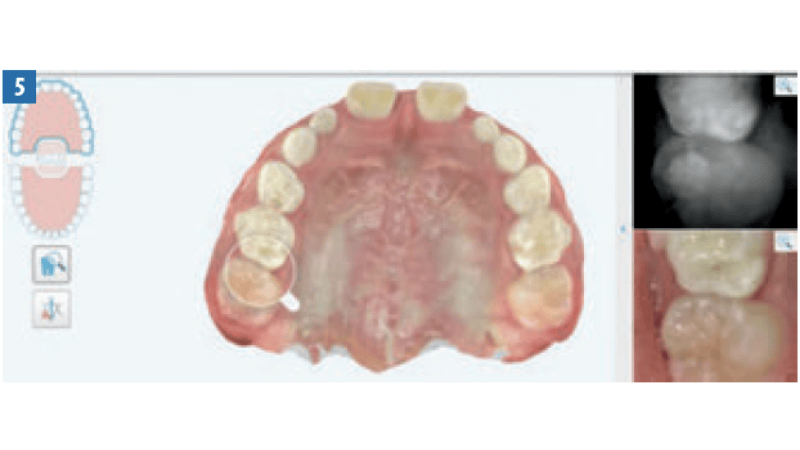

Streszczenie: W artykule przedstawiono opis leczenia 10-letniego pacjenta z jednostronnym zgryzem krzyżowym bocznym i stłoczeniem w łuku dolnym za pomocą ekspandera podniebiennego Invisalign®.

Summary: This article describes the treatment of a 10-year-old patient with a unilateral lateral crossbite and crowding in the lower arch using the Invisalign® palatal expander.

Wiele wad szkieletowych i skomplikowanych wad zgryzu wymaga ekspansji podniebienia i łuków zębowych. Stany te są tradycyjnie leczone za pomocą ruchomych i stałych ekspanderów, które wymagają zaangażowania ze strony pacjentów i ich rodziców. Aparaty te bywają przyczyną wizyt w trybie pilnym, gdy ulegną obluzowaniu lub uszkodzeniu bądź gdy rodzice mają problemy z przekręcaniem śruby lub nie są pewni, jak należy tego dokonać. Co więcej, w niektórych przypadkach dochodzi do demineralizacji tkanek twardych i stanów zapalnych podniebienia oraz dziąseł pod aparatami. System ekspandera podniebiennego Invisalign®to nowy ruchomy, skuteczny klinicznie1 aparat, obejmujący aktywne ekspandery [...]